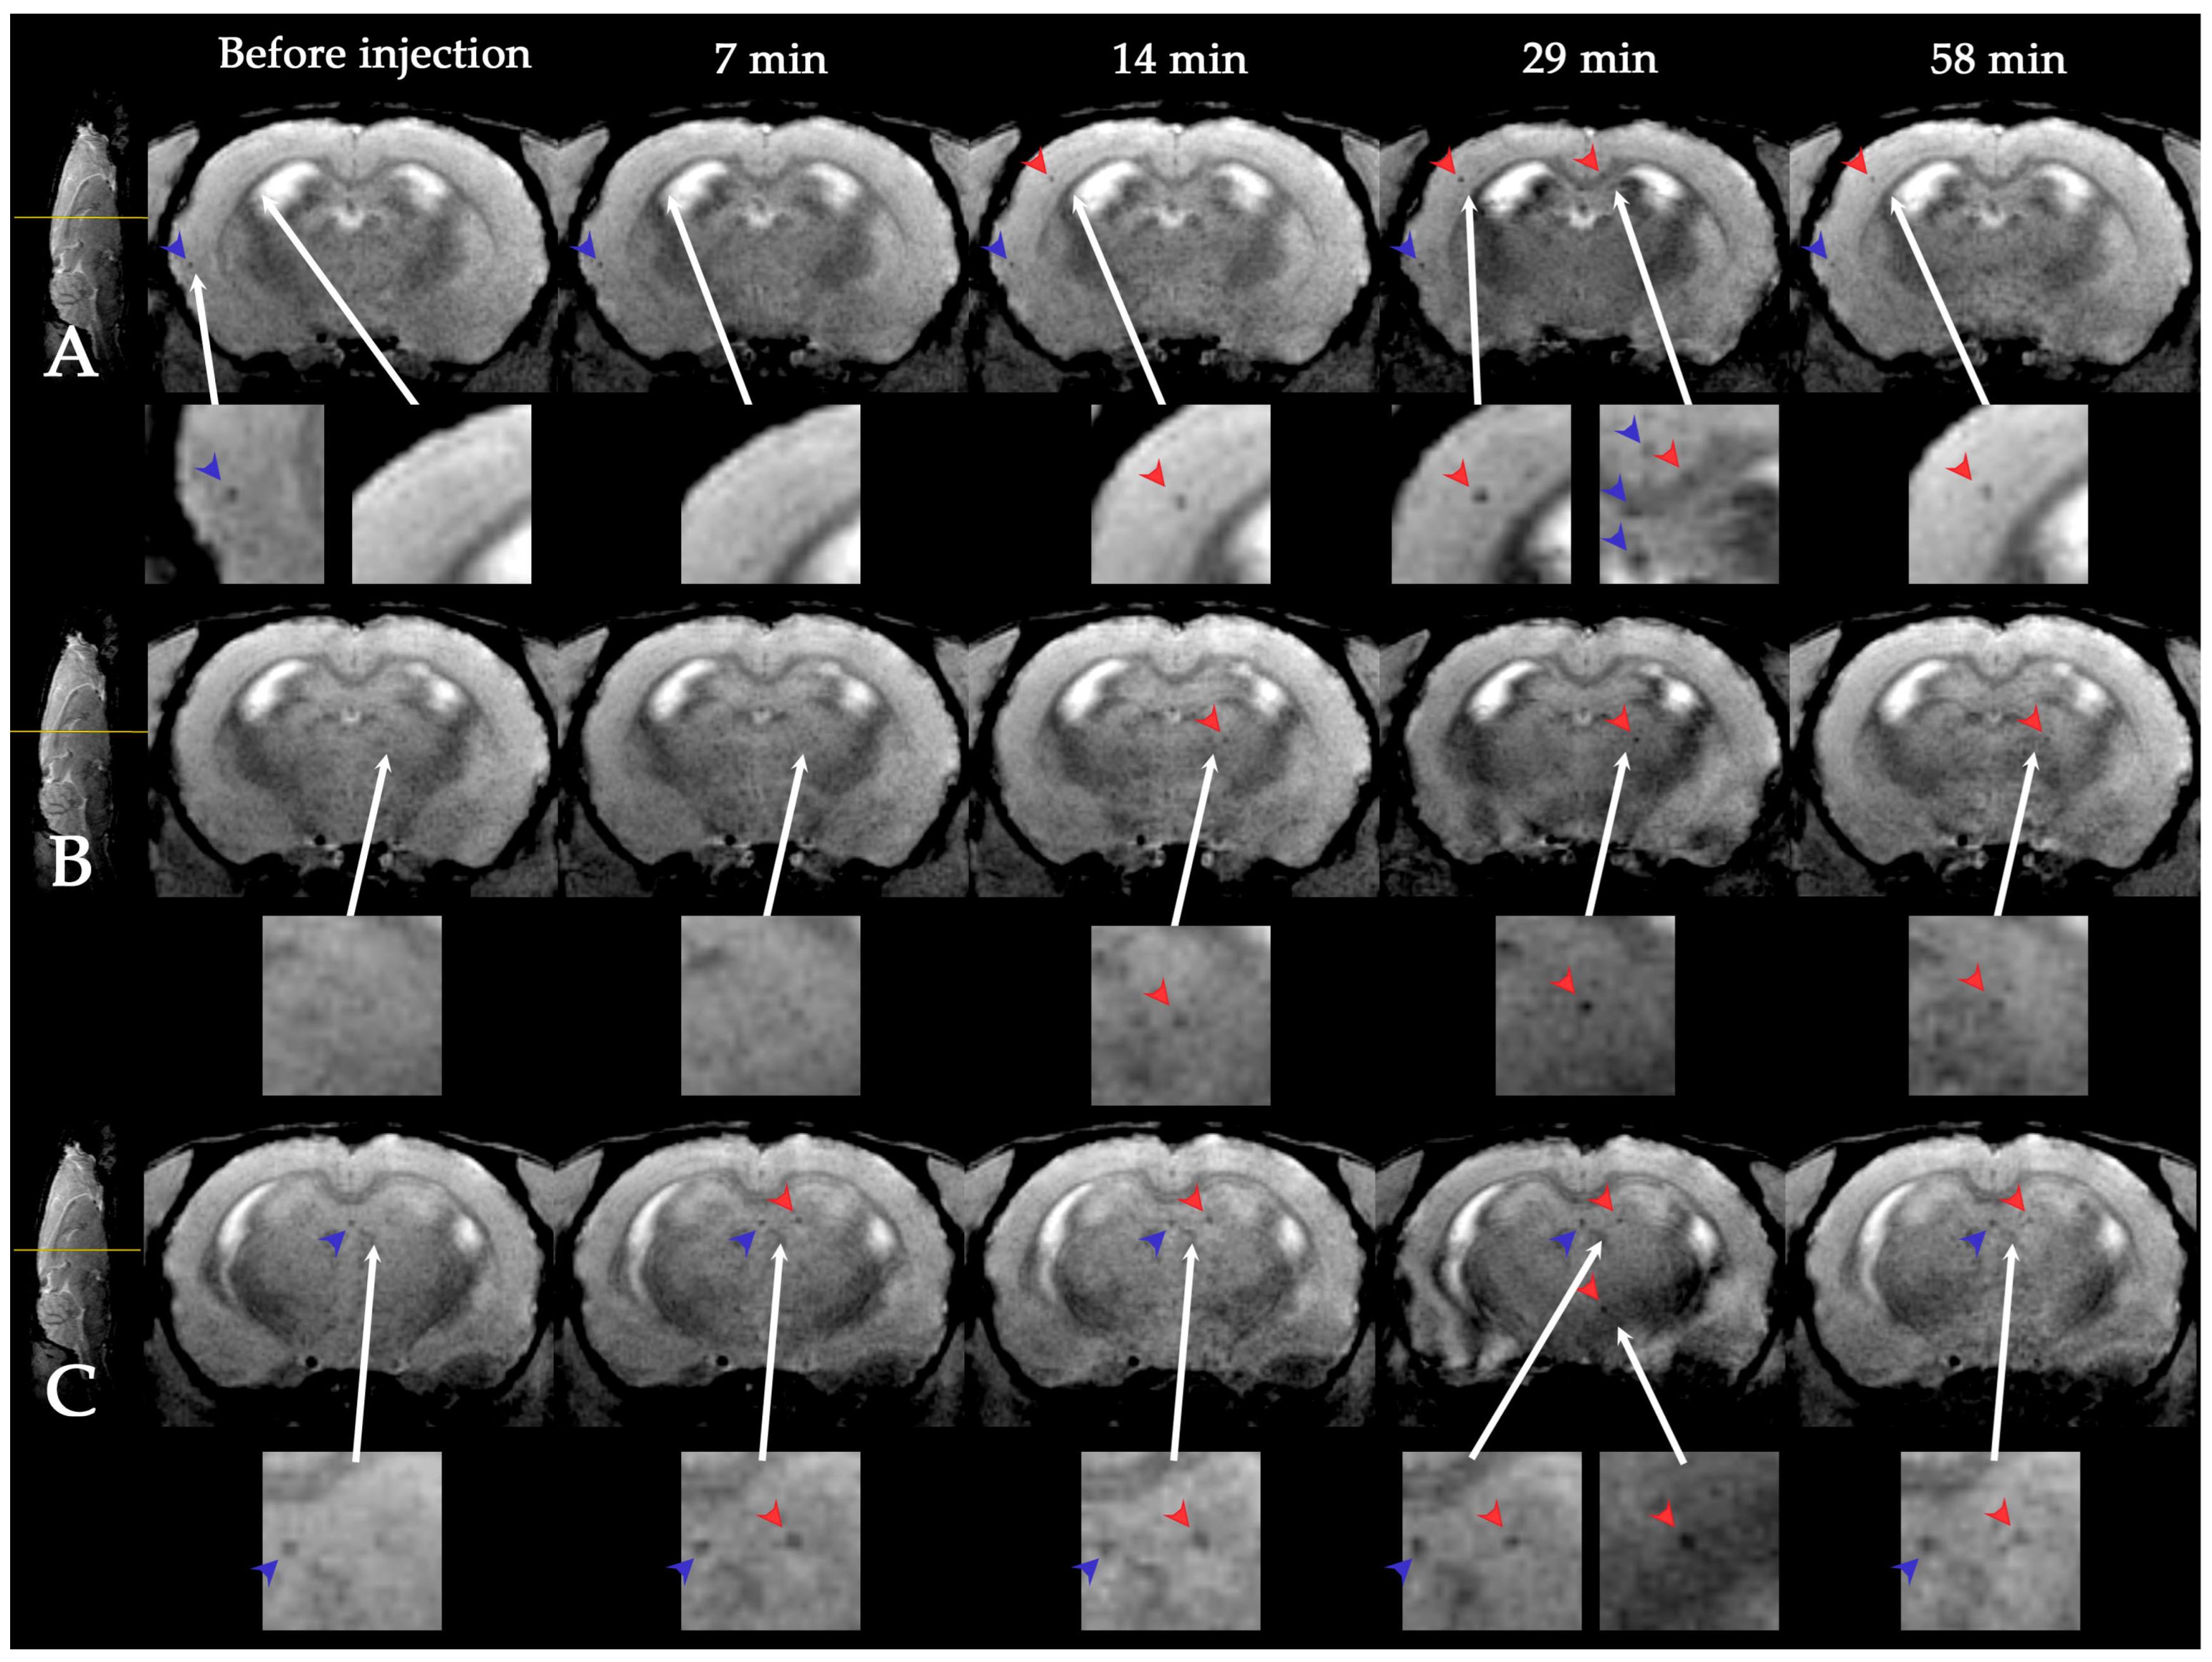

3.1. Dynamic MRI Distribution of MSCs in Ischemic Rat Brain after Intravenous Transplantation